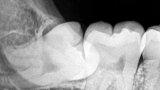

Источник: Nizil Shah/CC BY-SA 4.0